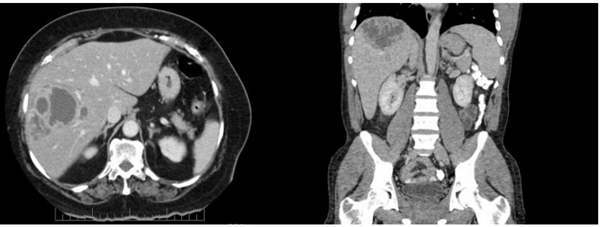

Paciente de 32 anos, sexo feminino, procurou o pronto-socorro por fraqueza, febre vespertina de até 39 ºC e dor em hipocôndrio direito há 4 semanas. Retornou da viagem de 1 semana ao Pará (proximidades de Santarém) 2 dias antes dos sintomas iniciarem. Exame físico: bom estado geral; anictérica; febril; hidratada; auscultas cardíaca e pulmonar normais; abdome doloroso à palpação em hipocôndrio direito; fígado palpável a 3 cm do rebordo costal direito; baço não palpável; algumas lesões de pele nas pernas. Exames laboratoriais: hemoglobina 11,9 g/dL; leucócitos 19.000/mm3; TGO 45UI/L; TGP 38UI/L; fosfatase alcalina 304 UI/L; gama-glutamiltransferase 268 UI/L; proteína C reativa 135. Tomografia computadorizada de abdômen apresentando a imagem a seguir:

Em relação ao caso, além de coletar hemoculturas, a conduta adequada é: